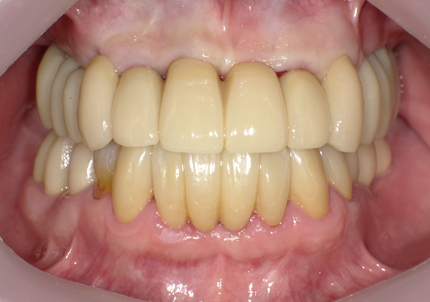

22.最終補綴物完成・装着口腔内写真(2021年1月)

23.自然な形態のインプラント歯頚部

適切な治療計画と治療技術を有することで、このような自然な形態のインプラント歯頚部を形成することができます。